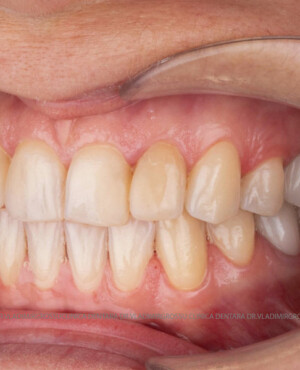

Restaurări cu coroane din zirconiu vs fațete ceramice

Atât fațetele ceramice (Emax sau 360) cât și coroanele din zirconiu sunt soluții estetice eficiente. Fațetele sunt indicate pacienților cu o poziție dentară relativ uniformă și dinți vitali, deoarece implică șlefuirea minimală a smalțului (0,4–0,7 mm) și fixarea adezivă sub coferdam. În cazurile cu dinți tratați endodontic, coroane pigmentate, proteze pe implanturi sau când este necesară o creștere semnificativă a ocluziei, se preferă coroanele din zirconiu.